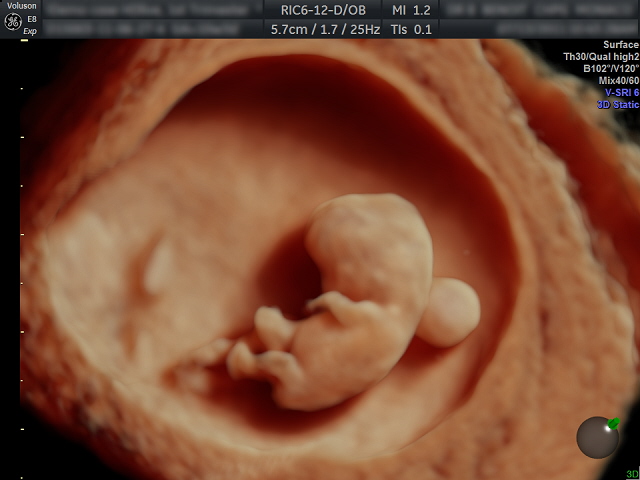

Ecografía. La ecografía es el método de exploración imprescindible en el ámbito del diagnóstico prenatal. Tiene unos momentos clave de aplicación:

En el primer trimestre. Nos permite detectar algunas imágenes consideradas "marcadores de cromosomopatías". La más válida y aceptada en los últimos años es la conocida como “translucencia nucal”, estructura visualizable en el dorso del feto entre la semana 11 y 14. Si supera ciertas dimensiones (3 mm.), deberíamos ofrecer la realización de prueba invasiva. Igualmente importante es visualizar el hueso nasal, pues su ausencia se ha relacionado con el Síndrome de Down.